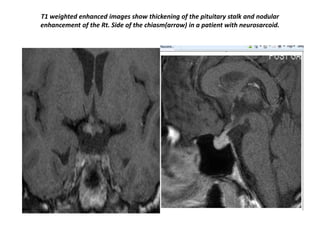

T1 weighted enhanced images show thickening of the pituitary stalk and nodular

enhancement of the Rt. Side of the chiasm(arrow) in a patient with neurosarcoid.

T1 weighted enhancedimages show thickening of the pituitary stalk and nodular enhancement of the Rt. Side of the chiasm(arrow) in a patient with neurosarcoid.